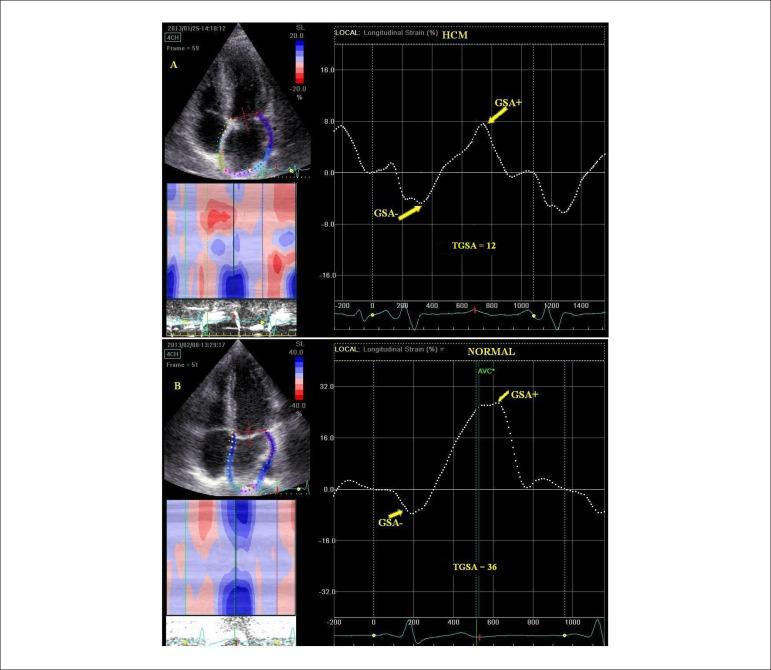

The assessment of left atrial (LA) function is used in various cardiovascular diseases. LA plays a complementary role in cardiac performance by modulating left ventricular (LV) function. Transthoracic two-dimensional (2D) phasic volumes and Doppler echocardiography can measure LA function non‑invasively. However, evaluation of LA deformation derived from 2D speckle tracking echocardiography (STE) is a new feasible and promising approach for assessment of LA mechanics. These parameters are able to detect subclinical LA dysfunction in different pathological condition. Normal ranges for LA deformation and cut-off values to diagnose LA dysfunction with different diseases have been reported, but data are still conflicting, probably because of some methodological and technical issues. This review highlights the importance of an unique standardized technique to assess the LA phasic functions by STE, and discusses recent studies on the most important clinical applications of this technique.

左心房(LA)功能评估应用于多种心血管疾病。LA通过调节左心室(LV)功能在心脏功能中发挥补充作用。经胸二维(2D)相位容积和多普勒超声心动图可无创测量LA功能。然而,基于二维斑点追踪超声心动图(STE)评估LA变形是一种评估LA力学的新的可行且有前景的方法。这些参数能够在不同病理状态下检测亚临床LA功能障碍。已有关于LA变形的正常范围以及诊断不同疾病LA功能障碍的临界值的报道,但数据仍存在冲突,这可能是由于一些方法学和技术问题。本综述强调了采用独特标准化技术通过STE评估LA相位功能的重要性,并讨论了关于该技术最重要临床应用的近期研究。